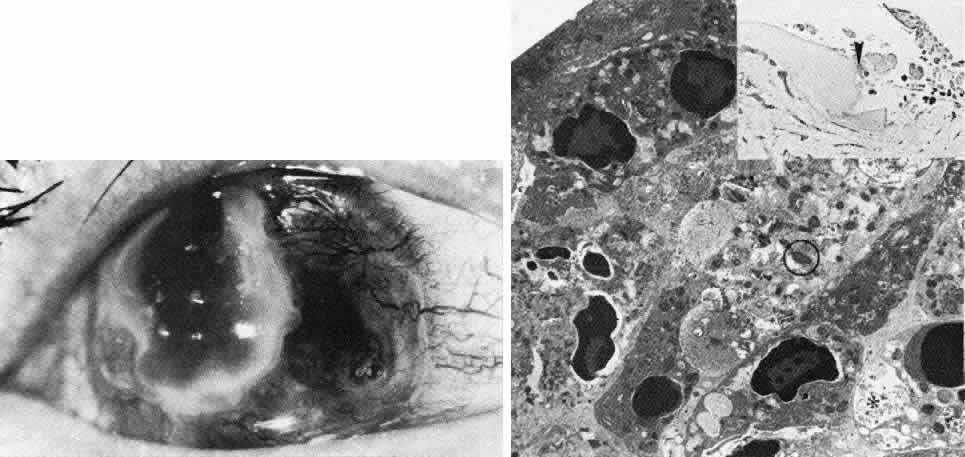

Fuchs' Dystrophy (Late Hereditary Endothelial Dystrophy)

Fuchs' dystrophy (Figs. 5 AND 17)185–189 is usually seen in the fifth or sixth decade of life, somewhat more commonly in women. It is bilateral and frequently of dominant inheritance.185,186,190 The fundamental defect is progressive deterioration of the endothelium. The endothelial cells in the adult human lack significant miotic capability, and as they undergo attrition, the surviving cell population must enlarge and spread to maintain an intact monolayer in order to remain functionally competent as a barrier and pump in maintaining corneal deturgescence. Thus, as in patients with cornea guttata, serial pachymetry and specular microscopy are helpful in following the disease process. Both discrete (guttate) and diffuse thickening of Descemet's membrane usually develop with progressive endothelial degeneration and dysfunction (Color Plate 1,K).187

Fig. 17. Late hereditary endothelial dystrophy (Fuchs). Top left. Clinical photograph illustrates epithelial bullae, scarring, and neovascularization, resulting from long-standing stromal edema. Top middle. Light microscopy demonstrates intraepithelial edema, thickening of the basement membrane, subepithelial bullae (*) and fibrocellular pannus with adjacent break in Bowman's layer (hematoxylin-eosin, × 350). Top right. Transmission electron micrograph of basal epithelial cells and Bowman's layer shows multilaminar basement membrane complexes (BM, the sequel of chronic epithelial edema (× 5000). Middle left. Transmission electron micrograph of posterior cornea shows unremarkable stroma and anterior Descemet's membrane, but remarkable thickening of posterior Descemet's membrane to 12 mm with additional superimposition of large guttata (G). The remaining endothelial cells (En) are severely degenerated and attenuated (× 5000). Middle right. By scanning electron microscopy, the comparable picture of disjointed, attenuated endothelium (En) and numerous exposed guttata (*) is apparent. Note the fibrous feltwork quality of the abnormal posterior Descemet's membrane (× 300). Bottom. High-magnification trans mission electron micrograph of guttata resolves its composition of fine filaments (circled), multiple segments of basement membrane material (*), and collagen in long-spacing configuration (arrowheads) (× 50,000). (Top left. Grayson M: Diseases of the Cornea, p 242. St. Louis, CV Mosby, 1979)

Clinically evident edema starts axially and spreads peripherally. As stromal edema progresses to involve the epithelium, microbullous elevations of the epithelium bring decreased visual acuity, and in time, bullous keratopathy erupts (Color Plate 1L). When these epithelial blisters rupture, the patient experiences a foreign body sensation or pain that may be relieved by lubricants, occlusion, or bandage soft contact lens. Ultimately, penetrating keratoplasty is required for both comfort and visual rehabilitation. In rare instances when keratoplasty is not indicated, cautery of Bowman's layer may give symptomatic relief. The course of Fuchs' dystrophy may be accelerated after cataract extraction or other intraocular surgery, and precautions should be exercised to minimize intraoperative trauma.

On histologic examination, the sequelae of chronic epithelial and stromal edema are prominent. Anteriorly, abnormalities of the basement membrane adhesion complexes develop because of repeated lift-off of the edematous epithelium.188 There are occasional breaks in Bowman's layer, and subepithelial debris and fibrovascular pannus collect in the zone of bullous edema. The most striking abnormality is diffuse thickening of Descemet's membrane (often to 20μm or more) with posteriorly projecting excrescences, corresponding to clinically apparent guttata. Histologic evidence of abnormal endothelial cell function is apparent many years before the clinical signs of corneal guttata and thickened Descemet's membrane appear.191